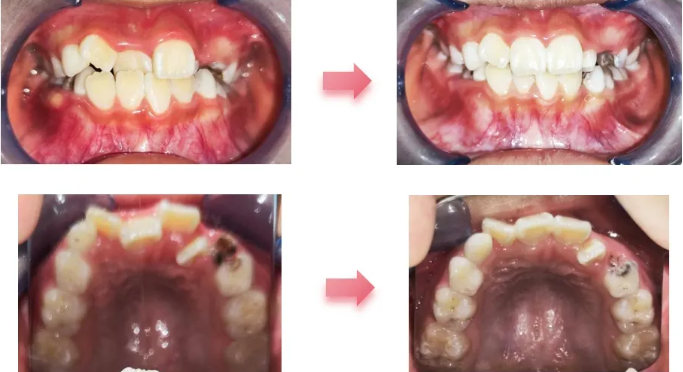

经过两个月的扩弓,杨妈妈带孩子复诊时惊喜地说,原本藏在里面的上门牙竟然自己来到了前面。医生向她解释,这是因为扩弓使原本被挤在后面的牙齿得以舒展归位了。扩弓到位后,又经过几个月的推上前牙唇向移动,上下前牙解除了颌干扰,排列也更加整齐美观了。经过医生的考量和杨妈妈、杨小酒的一致同意,结束了为期半年的替牙列期早矫,医生为小酒重新留存了一组颌面照,这一次,小酒恢复了往日灿烂的笑容。

(从X光片及口内可见左上尖牙将异位萌出,阻碍侧切牙排齐,并且拥挤量过大无法完全靠扩弓解决,左上侧切牙的扭转及全口牙列拥挤待替牙完成后进行二期固定矫治排齐)

(临床中下颌扩弓的效果多不理想,因此只进行了上颌扩弓,下颌牙弓发生了相应改建)